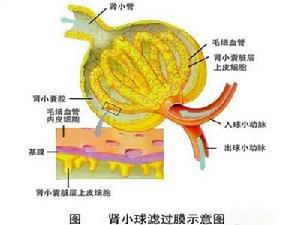

腎小球

腎小球疾病別名:急性腎炎,急性感染後腎小球腎炎,急性腎小球腎炎,acutepostinfectiousglomerulonephriti,acutepoststreptococcalglomerulonephritis,PSGN